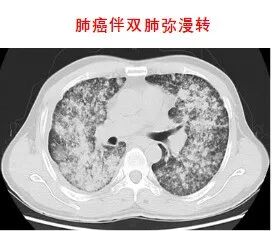

靶向治療,是在細胞分子水平,針對已經明確的致癌位點(該位點可以是腫瘤細胞內部的一個蛋白分子,也可以是一個基因片段的突變)進行靶向抗腫瘤治療。分子靶向治療具有特異性抗腫瘤作用,使腫瘤細胞特異性死亡,不會波及腫瘤周圍的正常組織,其療效增加,毒副作用明顯減少。